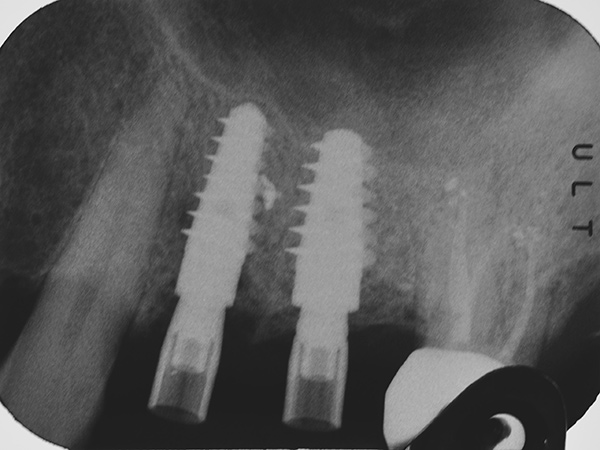

L’intervento ha previsto la progettazione di un impianto a carico immediato con sviluppo protesico digitale. Nello specifico, sono stati utilizzati i seguenti strumenti e tecnologie:

L’intervento è stato eseguito dal Dr. Alessando Casolino (Bologna) dello Studio del Dr. Casolino e la protesi è a cura dell’Odt. Massimo Venerato (Lab odontotecnico C.P. Dental) su MUA tipo A dritti dell’altezza di 1 mm.